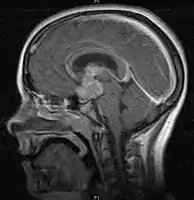

• Mainly located in midline structures, suprasellar region or pineal gland, also basal ganglia and hypothalamus

Location